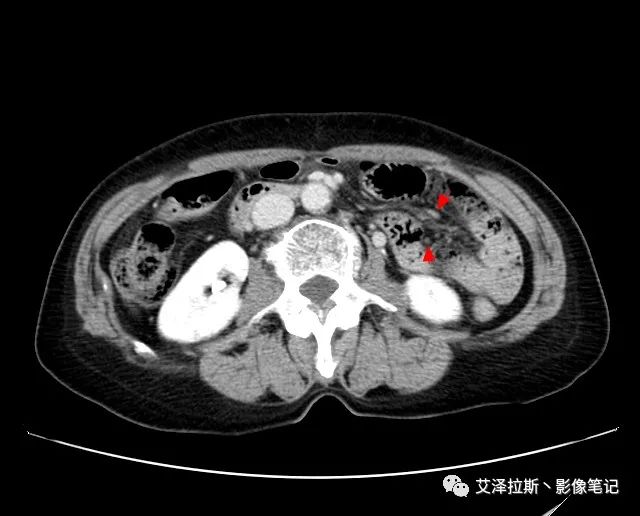

圖2 腫瘤

【影像所見】 胃竇部狹窄,胃壁環(huán)形增厚,小彎側(cè)見一巨大潰瘍,周圍伴“環(huán)堤征”,漿膜面不完整,胃周脂肪見網(wǎng)格狀條索影,病灶與肝臟左葉、胰腺鉤突脂肪間隙消失,增強(qiáng)掃描病灶明顯強(qiáng)化。引流區(qū)內(nèi)約15個區(qū)域淋巴結(jié)受累。

【診斷意見】 胃竇部胃癌(T4N3期) 該病例腫塊突破漿膜層,與肝臟左葉、胰腺鉤突分界不清,脂肪界面消失,定為T4期; 受累及的淋巴結(jié)為15個區(qū)域,定為N3; 有無遠(yuǎn)處轉(zhuǎn)移尚不明確,所以M期暫時無法確定。